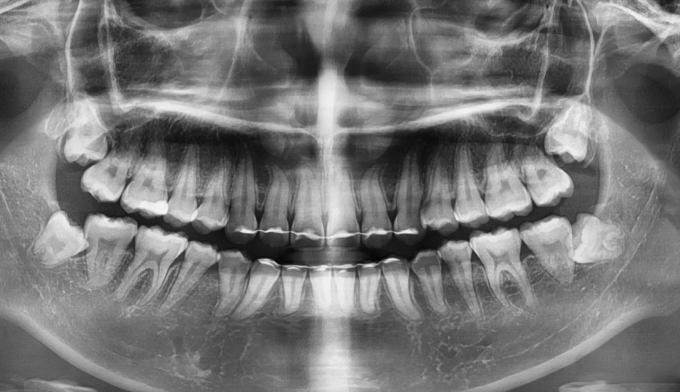

성장과정 중 어금니의 잘못된 맹출경로로 인해 쓰러지면서 나오는 경우가 종종 있습니다. 어금니가 쓰러지게 되면 해당부위에 음식이 저류되어 충치가 생기기 쉬워지며, 해당부위에 음식의 부패로 냄새와 함께 잇몸염증이 나타나기 쉽습니다. 나머지 부위에 대한 교정치료 욕구가 없다면 해당 어금니부위만 부분교정을 통해 어금니를 바로 세워줄 수 있습니다. 교정치료는 9개월 소요되었습니다.